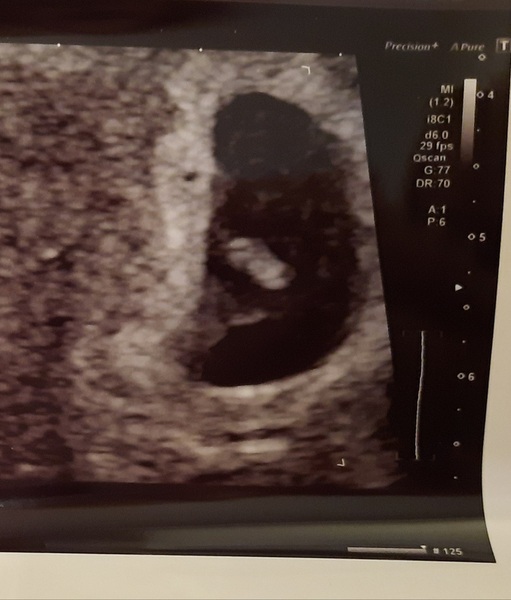

BertieBotts · 21/12/2020 09:59

Appointment went really well! I am 2 days less than we thought - 6+0 instead of 6+2, which puts me back to 16th Aug. But there is a heartbeat and everything looks good apparently!